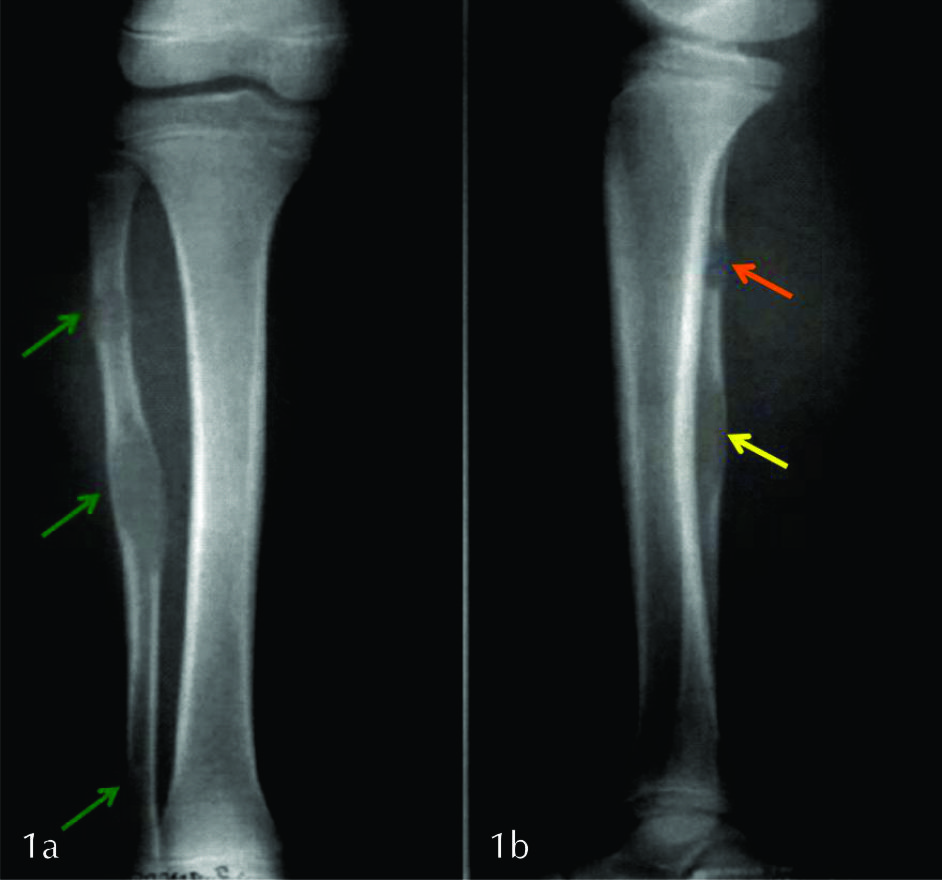

Se solicitó radiografía simple de pierna derecha en proyección frontal y de perfil (Ver fig. 1 y 2), que se completó con TC sin contraste a pedido del traumatólogo tratante (Ver fig. 3).

Ambos estudios constataron la presencia de tres lesiones líticas de baja agresividad, con características imagenológicas de DF. Solamente la lesión proximal presentó reacción perióstica de tipo ininterrumpido asociado a un trazo de fractura patológico.

Figura 1

Radiografía de pierna derecha

a) frente, b) perfil.

Se identifican tres lesiones líticas (flechas verdes) diafisarias y metafiso diafisarias, localizadas en la medular del tercio superior, medio e inferior del peroné. Presentan bordes geográficos sin anillo esclerótico y zona de transición estrecha (lesiones tipo 1b). Véase como expanden y adelgazan la cortical (flecha amarilla). No posee matriz radiológicamente visible, componente de partes blandas ni compromiso articular por este método. La lesión superior presenta un trazo horizontal esclerótico que podría corresponder a fractura evolucionada (flecha naranja).